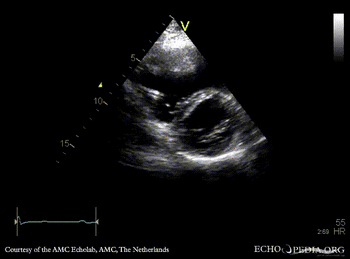

ARVD

Courtesy of: AMC Echolab, AMC, The Netherlands

A4CH: dilated right ventricle, reduced systolic function